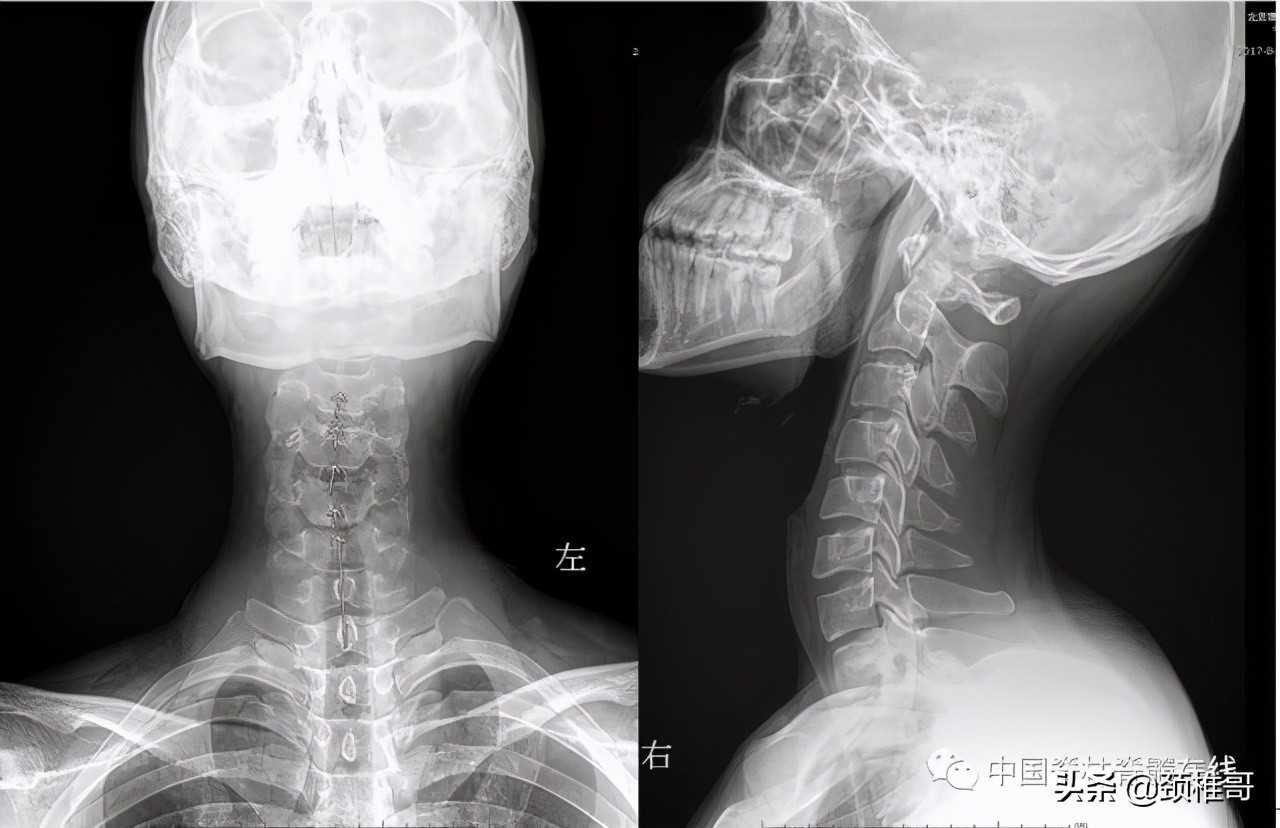

交感神经型颈椎病患者:颈椎MRI颈椎间盘正常、颈椎生理曲度异常

颈椎正侧位:序列 欠佳 动力位:颈椎3-6各个节段之间不稳